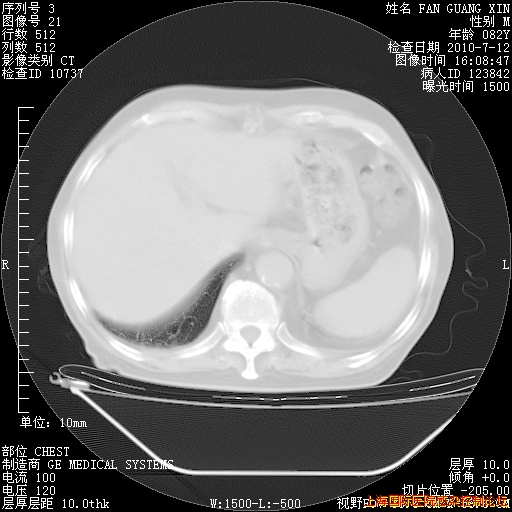

今天CT

整整相隔30天的肺部CT好像有所好转啊。甲强龙减量第3天,需要观察体温。